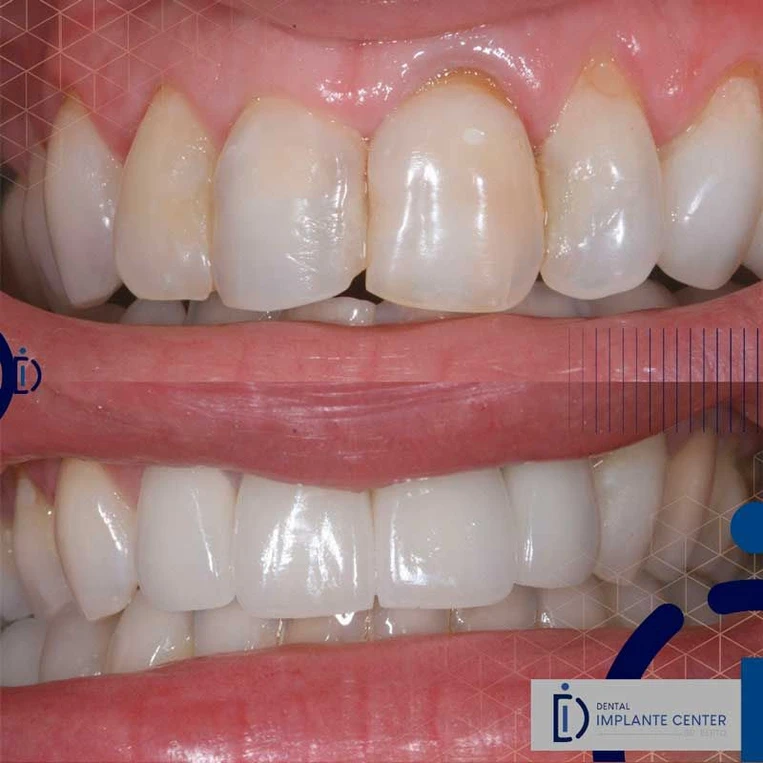

O protocolo dentário definitivo refere-se ao planejamento e execução do tratamento com a prótese final, que será a solução duradoura para o paciente. Após a fase inicial de implantes, cirurgias e possíveis tratamentos de tecidos, chega o momento de fazer a moldagem final, escolher a cor e o tipo de material da prótese, e realizar a instalação do sorriso definitivo. Esse procedimento garante uma estética natural, funcionalidade e durabilidade, proporcionando ao paciente uma melhora significativa na qualidade de vida. Se quiser saber mais detalhes sobre o processo ou etapas específicas, estou aqui para ajudar!

Técnica moderna que restabelece a função de mastigação e estética em poucos dias. Indicada para pacientes que perderam um dente, dois dentes ou todos os dentes.